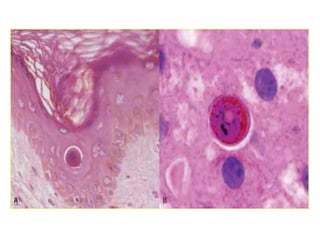

MORPHOLOGY 0F APOPTOSIS

• Cell shrinkage

• Chromatin

condensation

• Formation of

cytoplasmic blebs

and apoptotic bodies

• Phagocytosis of

apoptotic cells or cell

bodies usually by

macrophages.